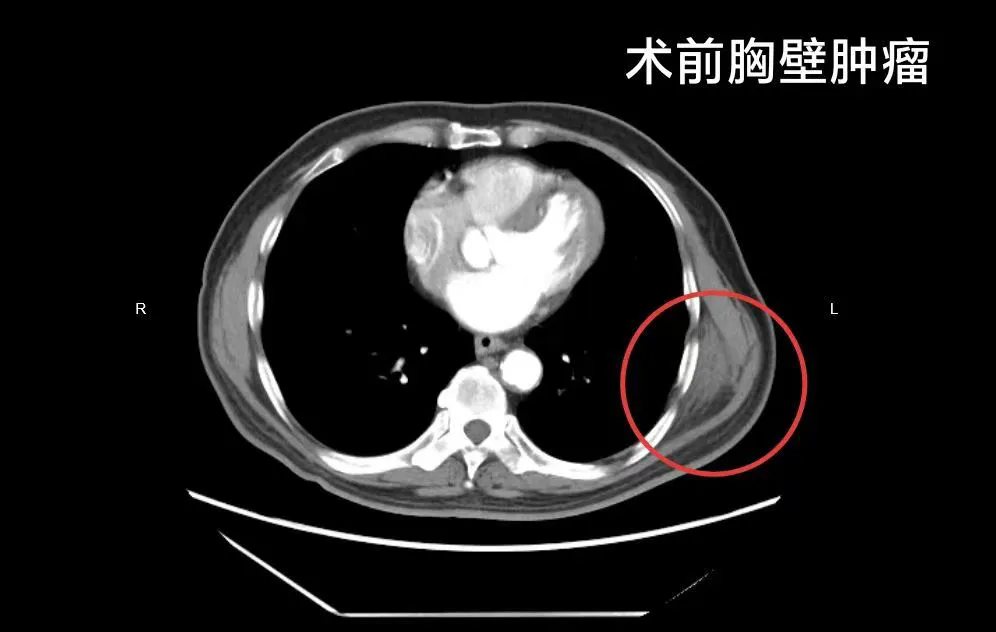

患者为一名退休职员,3个月前发现背部左侧肩胛下区出现2枚肿物,近段时间左侧肿物持续增大,遂前往秦皇岛市第三医院外二科就诊。经体表软组织超声检查显示,患者左侧肩胛下角内侧见梭形软组织密度影约67*25mm,边界不清,临床考虑为弹力纤维瘤。结合患者存在8年高血压病史、7年冠心病病史,且有心脏支架手术史的特殊身体情况,胡博医生团队经过全面评估与周密研讨,决定采用当前先进的腔镜下微创切除方案。

该手术借鉴国内某著名医学中心医院完成的世界首例“全腔镜三孔隧道式肩胛骨下胸壁肿瘤切除术”技术理念,通过微小切口建立操作通道,如同“挖隧道”般精准定位肿瘤组织并完整切除。相较于传统开放手术,腔镜下胸壁肿瘤切除术具有创伤小、恢复快、疼痛轻的显著优势,尤其适合老年患者及合并基础疾病的患者,能最大程度降低手术风险与术后并发症概率。目前,患者术后状态平稳,各项生命体征正常,正在顺利康复中。